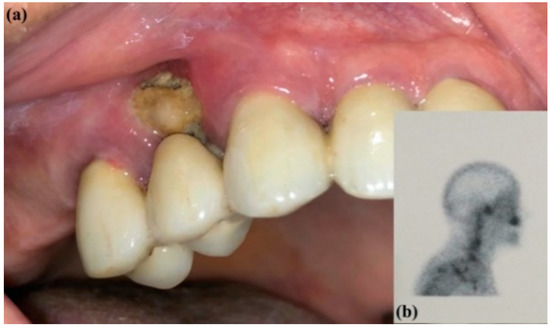

Management of Medication-Related Osteonecrosis of the Jaw (MRONJ) Using Leukocyte- and Platelet-Rich Fibrin (L-PRF) and Photobiomodulation: A Retrospective Study